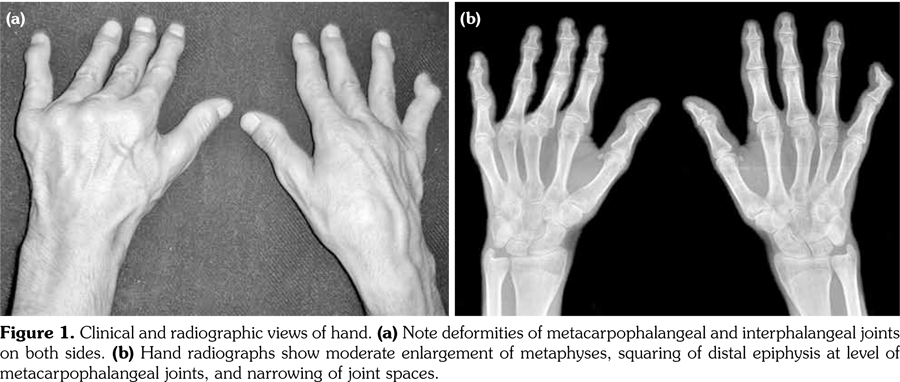

Radiographs of the hands showed enlargement of metaphyses, flattening of epiphyses, and narrowing of joint spaces with no erosions. Lateral radiograph of the foot revealed bilateral large ossified trigonum attached to the talus (mega os trigonum) (Figure 3). Radiographs of the spine showed increased kyphosis, generalized platyspondyly particularly at the thoracolumbar junction, and irregularity of the vertebral end- plates (Figure 4). Magnetic resonance imaging of thoracolumbar spine demonstrated irregularity in vertebral end-plates, multiple disk herniations, and platyspondyly (Figure 5). Dynamic contrast- enhanced magnetic resonance imaging of the wrist did not reveal any signs of synovial inflammation.

Clinical features of PPD have been described in several reports.(9-11) The radiographic features include varying degrees of epiphyseal involvement with enlargement of the epi-metaphyseal region, progressive joint narrowing, generalized platyspondyly, multiple intervertebral herniations, kyphoscoliosis, mega os trigonum and bone destruction with aging.(2,6,10) Our patient had progressive restriction of several joints, IP enlargements, dysplastic bone/cartilage changes, mega os trigonum and platyspondyly, with normal acute phase reactants. The presence of dysmorphic features and the absence of inflammatory signs should alert the physicians for the possible hereditary dysplasias like PPD.